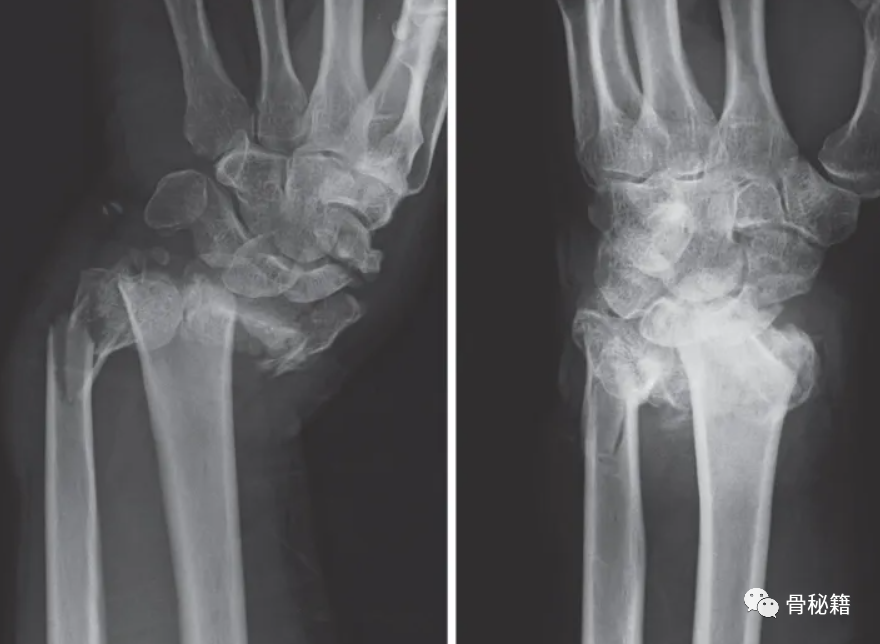

需要注意的要点:如果桡骨复位不佳,可能导致下尺桡关节匹配问题及相关韧带松弛最终带来相关症状,注意看桡骨尺侧轴线的位置